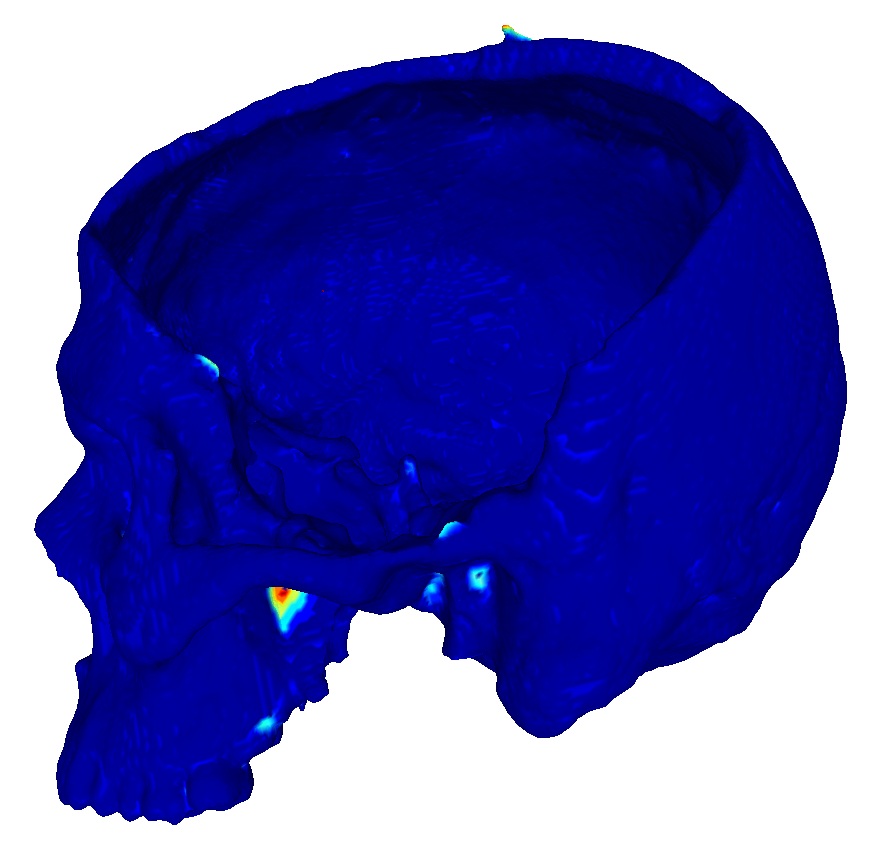

22 scans were randomly selected as test subjects for the experiment, leaving 177 skulls for model training. Using convolutional kernels of size 3 in all the CNN models results in the 3D model having the same number of trainable parameters as the sum of the three orthogonal 2D models. The comparison between the MV ensemble and the 3D approach can therefore be considered an ablation study to an extent. CutCNN models also have a similar number of parameters, the only difference being the final edge probability output layer. Quantitative comparison of results of each method are presented in Figure 4 and Table 1. Further qualitative results are shown in Figure 5 and 1.

CutCNN segmentation framework resulted in a performance gain in all cases in terms of every metric used in the experiment over standard CNN approaches. The output of CNN object probability map often contains errors near external objects or smaller tissue defects as these are scarce in the training data distribution. However, the graph-cut optimization guides the resulting binary segmentation towards a spatially consistent and compact shape, often eliminating these artifacts if a detected edge corresponds mostly to the correct object boundary. This effect is further illustrated in Fig. 1.

Our second observation is that using 3D convolutional kernels has a rather small effect on the final segmentation precision quantitatively compared to the MV approach. However, although the quantitative difference is small, for applications in medical additive manufacturing, it is important to avoid ragged segmentation output which may result from MV CNN in areas of lower model certainty. These include for example teeth, which are challenging to detect, especially when the lower and upper teeth are in contact (see Figure 5 a), or maxillary sinus, which is often enclosed in order to improve mechanical stability of the manufactured model (see Figure 5 b). Therefore, 3D U-nets are often considered necessary to avoid these discontinuities caused by slice-by-slice processing.

However, this artifact can also be addressed by employing the CutCNN framework since ragged segmentation boundary introduces a high boundary-term penalization during optimization and it is therefore avoided in the final binary segmentation. Thus, employing CutCNN allows the decision between 3D or multi-view approach to be merely a technical choice. Using 2D models can offer some advantages, such as faster training of deeper models with less overfitting [10].